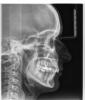

an_ver Опубликовано 19 июня, 2013 Поделиться Опубликовано 19 июня, 2013 Предистория такая.....П-ка обратилась к ортодонту по поводу (выступающего) клыка (23).Было проведено снятие слепков, ТРГ, ОПТГ не делалось,выставили 24, залепили Даймон на в/ч, через 8-9 месяцев готово((((. Обратилась ко мне через 2 года....ц.линия ушла (а может ее и не было) в суставах дискомфорт....Что думаете по этому случаю,коллеги? П-ка хочет все красиво Ссылка на комментарий

Премоляр Опубликовано 19 июня, 2013 Поделиться Опубликовано 19 июня, 2013 (изменено) Одностороннее удаление всегда предусматривает асимметрию и последующее сужение в.ч....суженная в.ч. блокирует н.ч.,вызывая(или не вызывая) так называемую "дисфункцию ВНЧС" Без соответствующего симметричного удаления симметрию не получить. Удалив 14 например,ср.линию "вернем на место ", но еще более уменьшим в.ч.,еще больше заблокируем н.ч.Соответственно,потребуется семметричное удаление и на н.ч....и т.д..Разумеется,возможно восстановить симметрию за счет создания места для 24. Это возможно.П.с. Деймон,8 мес.,одностороннее удаление,лечение на одной челюсти...Классика жанра. Сразу готовят пациента к перелечиванию Изменено 19 июня, 2013 пользователем Премоляр 3 Ссылка на комментарий

Викторовна575 Опубликовано 5 июня, 2014 Поделиться Опубликовано 5 июня, 2014 В результате одностороннего удаления произошло уплощение переднего отдела верхней зубной дуги, преимущественно слева,соответственно суставная головка левого ВНЧС еще больше сместилась дистально,создавая компрессию на биламинарную зону,отсюда и дискомфорт в области ВНЧС,я бы удалила 8-е на в\ч ,по крайней мере справа-точно,раскрыла промежуток для 14,чтоб восстановить симметрию в/ч,выровнить окклюзионные кривые,тяги-саморотация н/ч,даже если сохранится небольшая сагиттальная щель-для сустава это более благоприятно,а вообще, хорошо б еще КТ ВНЧС Ссылка на комментарий